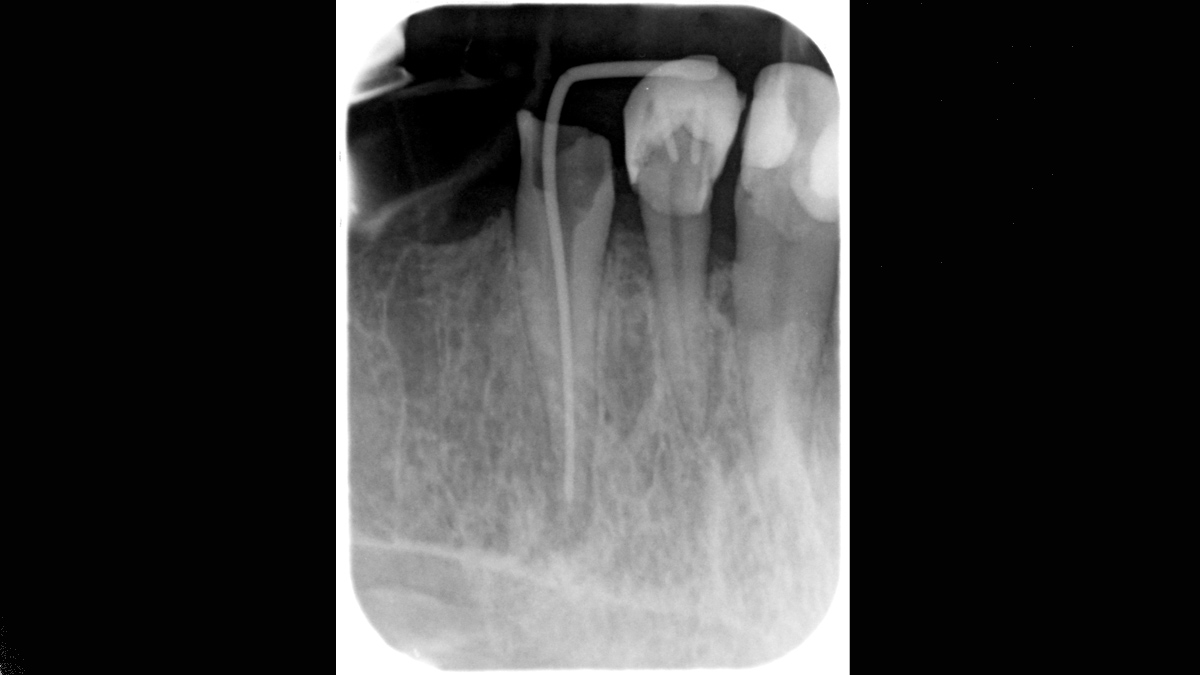

Xios Scan provides a gentle, easy introduction into the world of digital X-ray imaging. If you want to switch from film to digital without having to give up your tried-and-true working methods, imaging plate technology offers you a myriad of possibilities. You can experience many of the advantages of digital imaging without a darkroom and chemicals while your team continues its regular workflow.

The Xios Scan integrates seamlessly with the Dentsply Sirona X-ray units and software to deliver better, safer and faster intraoral diagnostics.